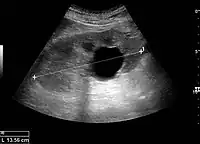

A very small (8 mm) simple renal cyst.

Bosniak II cyst at the lower pole of right kidney with septations within.